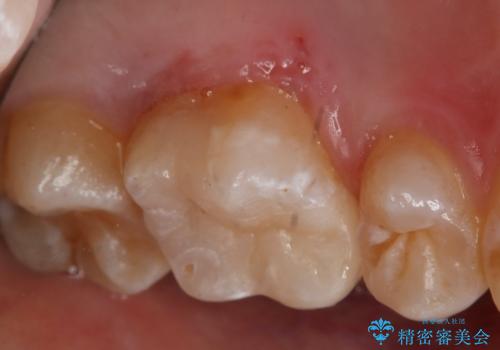

- 左上6番の銀歯のやり変えを希望し来院された患者様です。

切削量・形態を考慮し、セラミックインレーでの治療を計画しました。